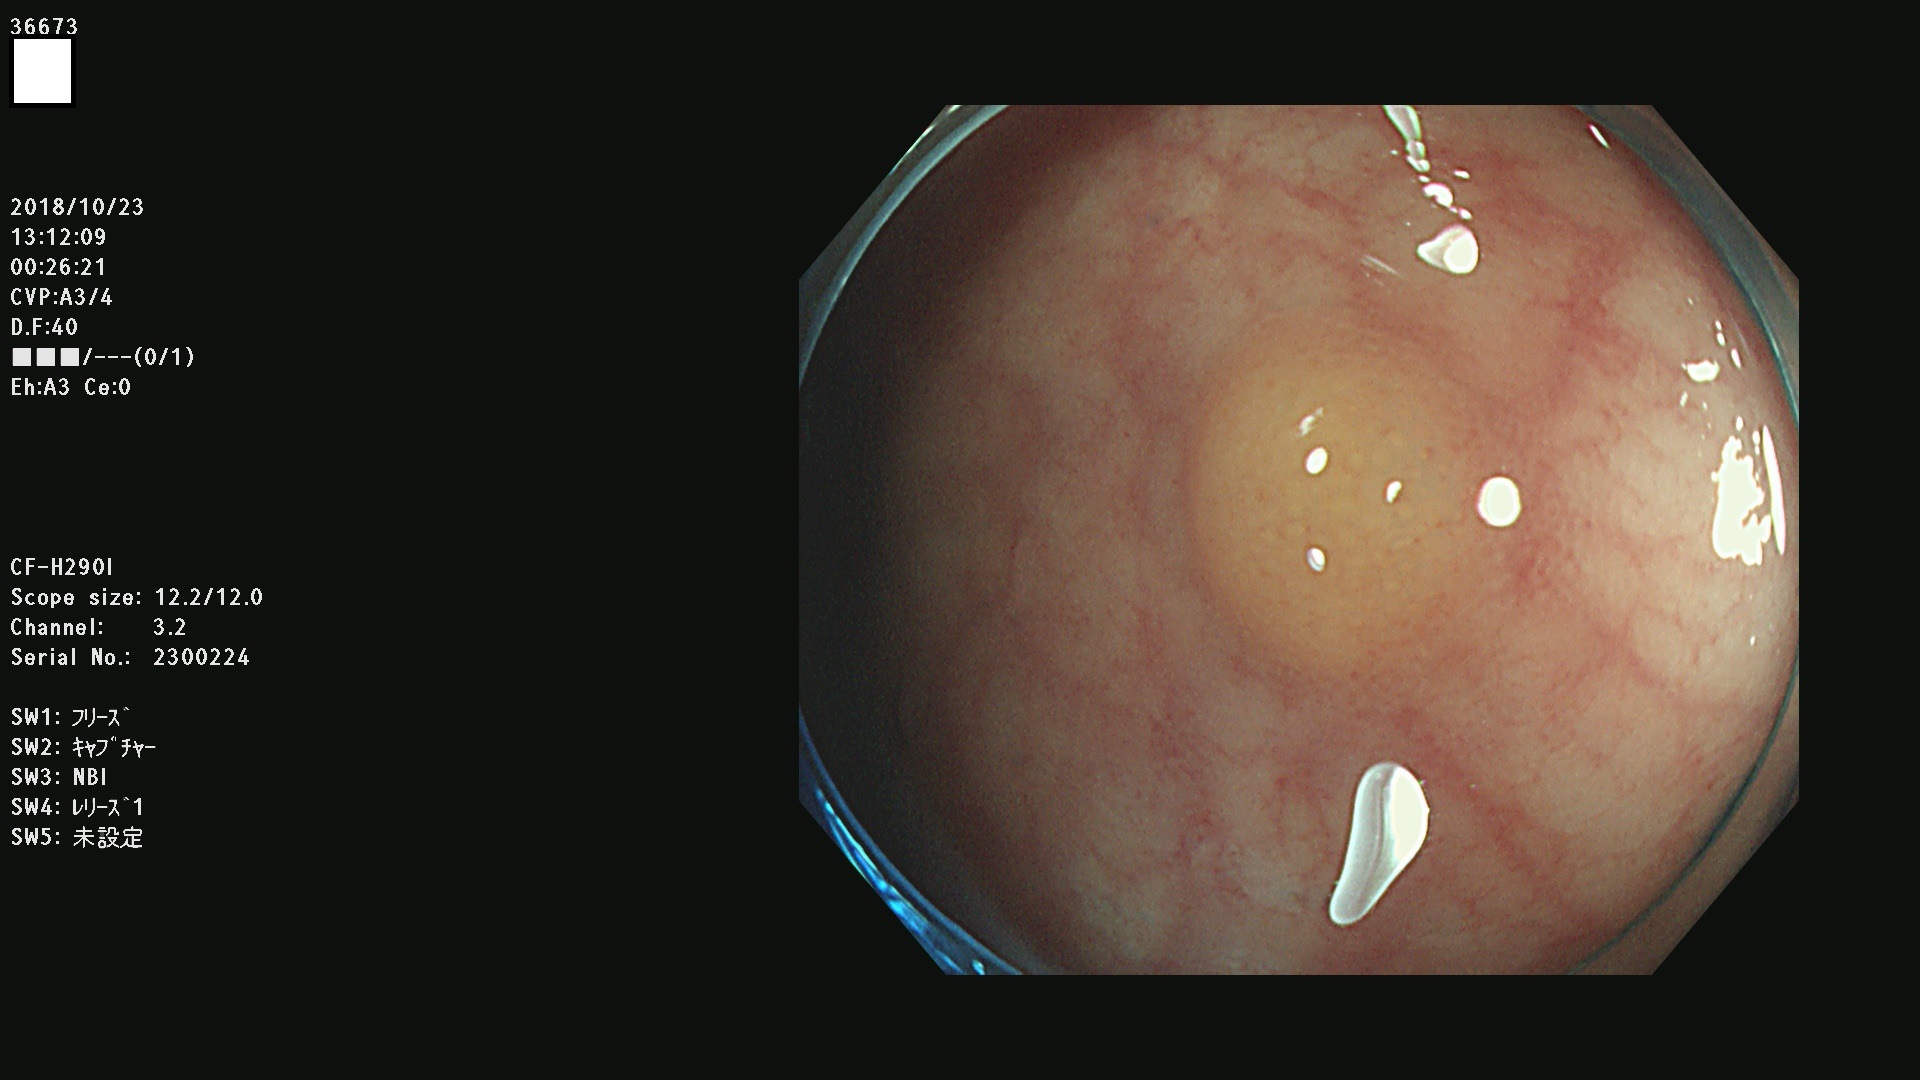

36600 36601 36603 36605 36606 36608 36609 36610 36611 36612 36613 36615 36617 36620 36621 36624 36625 36626 36627 36628 36629 36631(SSAPのみ) 36632 36633 36634 36636(SSAPのみ) 36637(SSAPのみ) 36639 36640 36642 36643 36644 36646 36647 36648 36649(SSAPのみ) 36650(SSAPのみ) 36652 36653 36654 36655(SSAPのみ) 36656 36657 36658 36659 36660 36661(SSAPのみ) 36665 36668 36669 36672 36673 36676 36677 36678 36679 36681 36682 36683 36684 36685 36687(SSAPのみ) 36691 36692 36693 36694 36695 36696 36697 36699(SSAPのみ)